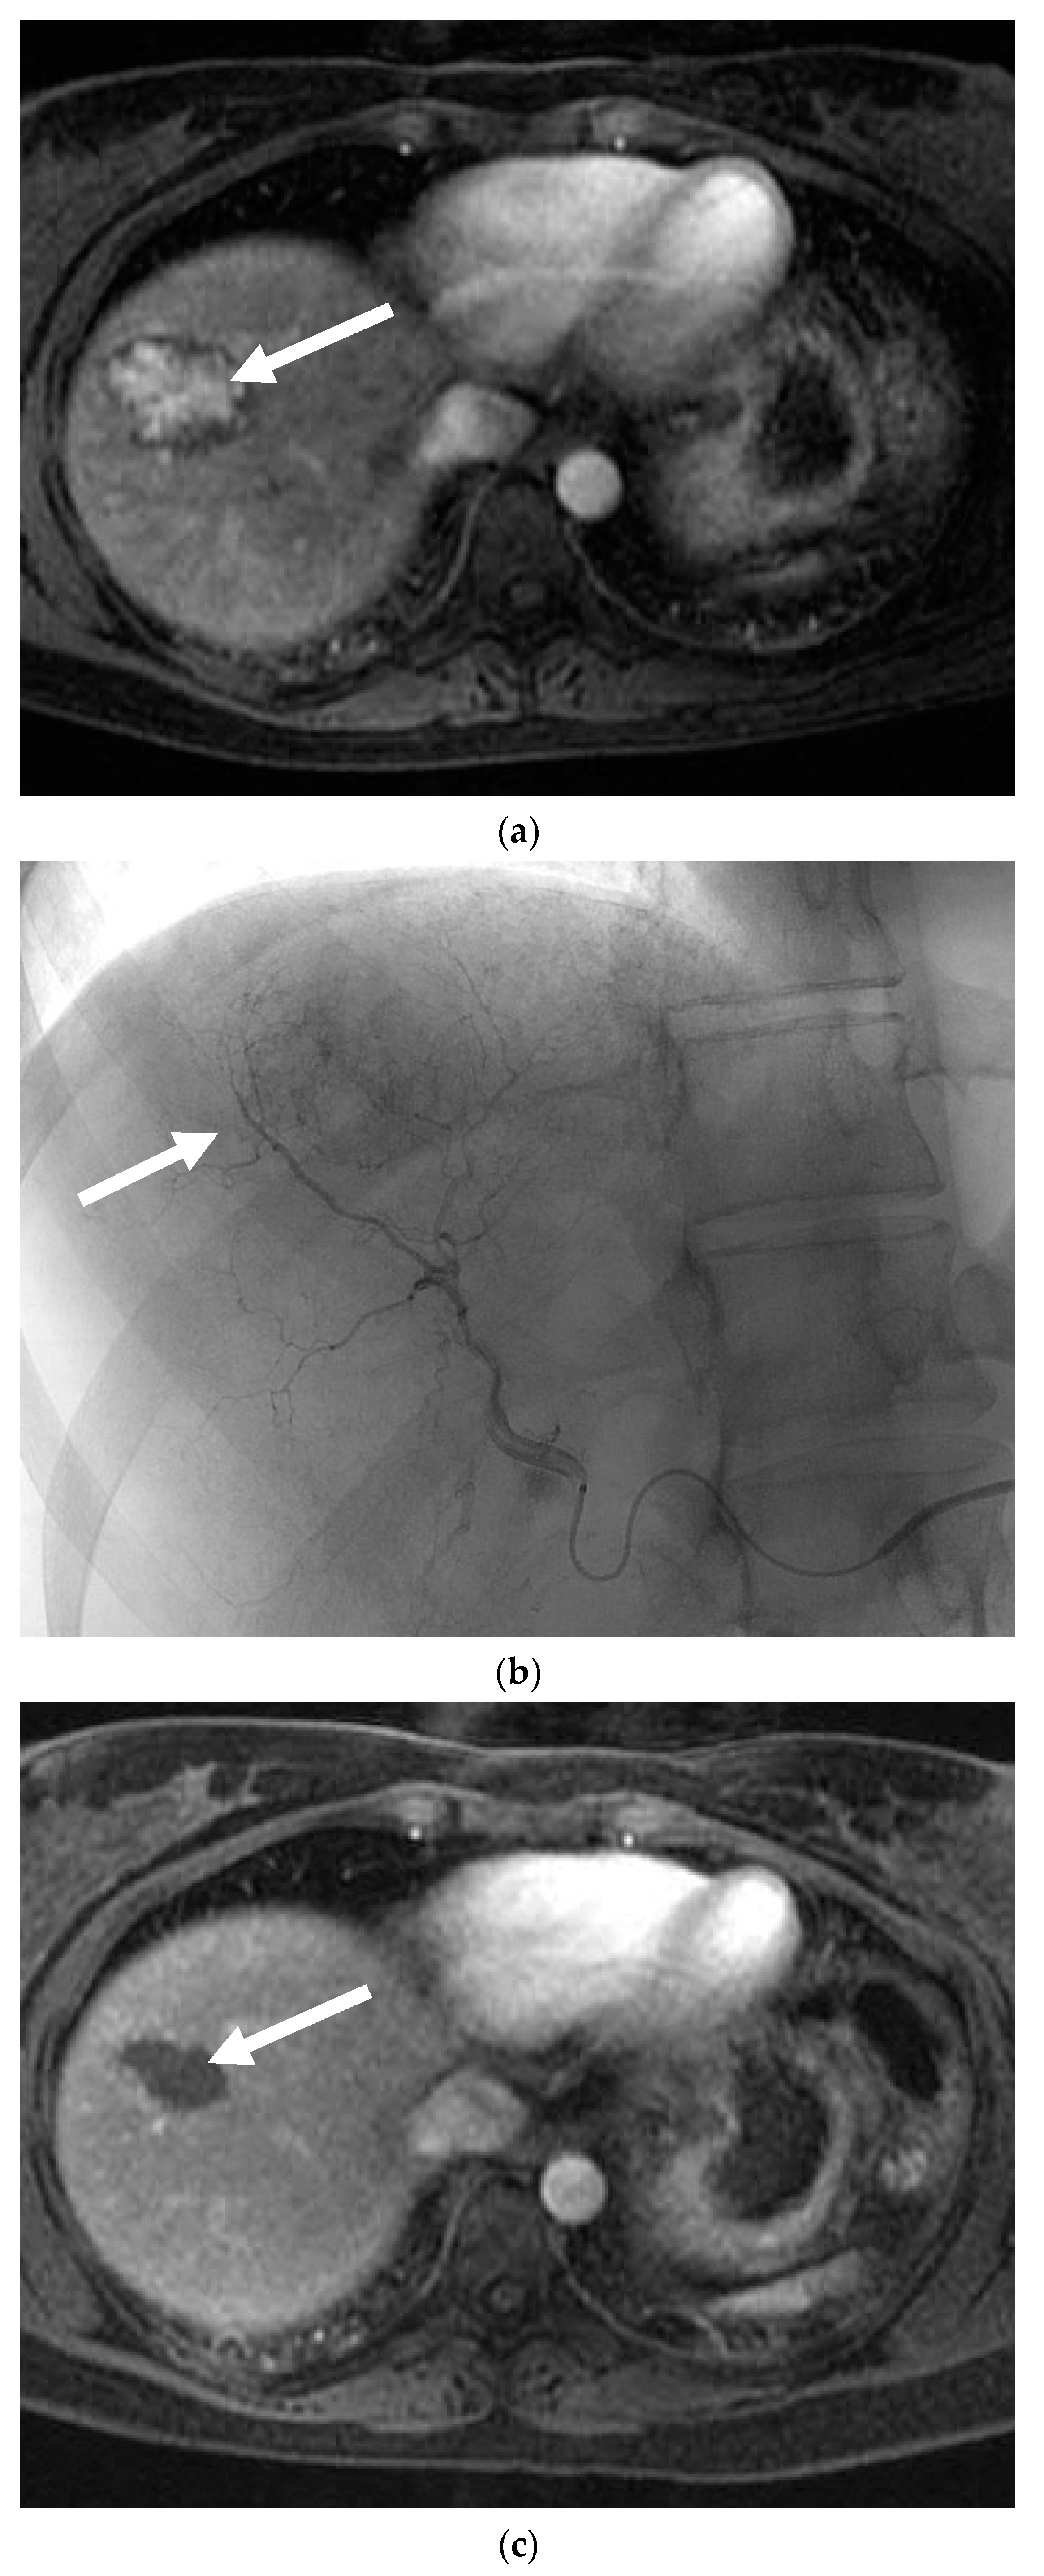

Figure 2.

A 24-year-old female with focal nodular hyperplasia (FNH) and right upper quadrant pain. (a) Magnetic resonance imaging (MRI) with contrast demonstrates a hypervascular lesion in segments 4 and 5 (solid white arrow). Twenty-minute delayed images showed continued enhancement (not shown). (b) Angiogram reveals segment 4 and segment 5 arteries that feed a hypervascular mass. Each artery was infused with 200 and 300 µm PVA particles until stasis. (c) Post-embolization angiogram shows no flow to the FNH. (d) MRI with contrast one month after embolization reveals no residual enhancement and a decrease in the size of the FNH (solid white arrow). The patient’s pain resolved following the embolization.